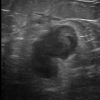

Di căn vú

Di căn vú - Ảnh 4

» Thông tin: Nữ giới – 70 tuổi.

» Lâm sàng: Khối tuyến vú / K hắc tố.